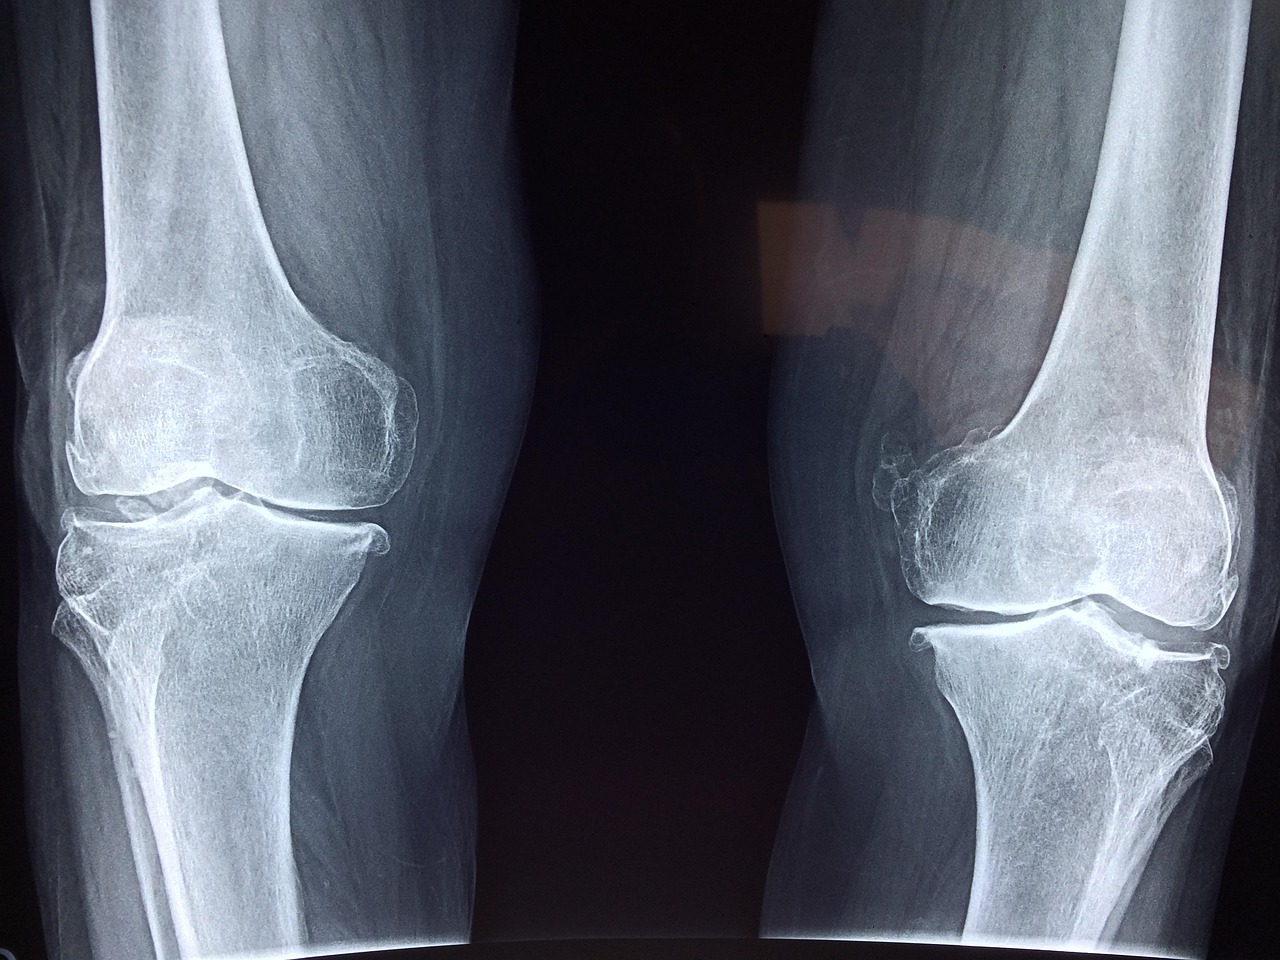

One cutting-edge innovation in injury assessment is MRI scanning technology. This non-invasive approach allows medical professionals to visualize internal injuries without surgical intervention. Utilizing 3D imaging greatly enhances the accuracy of diagnoses, providing insight into the extent of soft tissue injuries and bone fractures. Additionally, ultrasound technology is gaining traction as it can quickly assess joint injuries, offering immediate feedback to sports physicians. Medical personnel can use ultrasound for guided injection therapy, providing targeted relief for conditions like tendinitis. Moreover, advanced laboratory testing can identify specific biomarkers that indicate injury risk in an athlete, paving the way for tailored training regimens. This blend of technology not only aids in detecting ongoing problems but also provides data necessary for long-term athlete monitoring. Coaches and trainers can adjust training intensities based on an athlete’s biomechanical data, enhancing performance while warding off injuries. Emphasizing preventive care through technology continues to reshape the sporting landscape while keeping athletes safe. As technology progresses, its application will only continue to grow, delivering better insights into injury prevention and treatment for speed skaters.